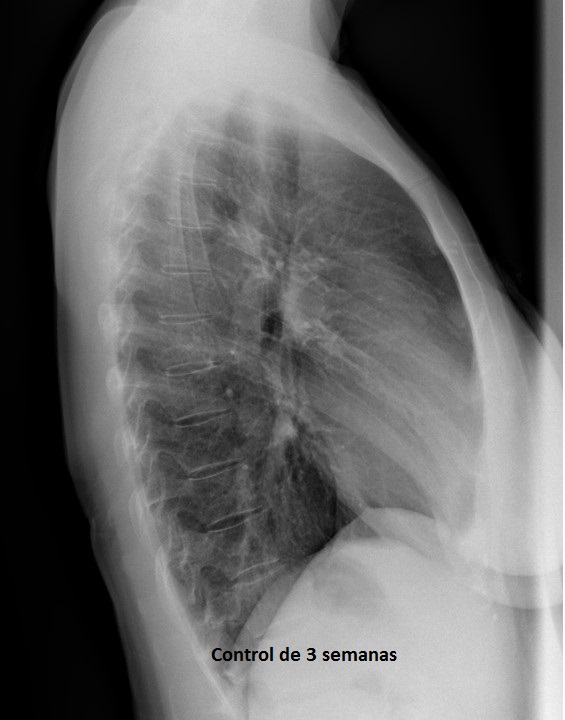

DIAGNÓSTICO FINAL: Neumonía en la base pulmonar izquierda.

En este caso, a la paciente se le realizó una placa de control a las 3 semanas, en la que no había persistencia de neumonía, por lo que se considera recuperada. En otros casos, donde la patología persiste tras el tratamiento preciso y donde haya factores de riesgo (consumo de tabaco, sospecha de neumoconiosis o fibrosis pulmonares), se plantea realizar otro tipo de técnicas de imagen, como TAC, para conocer la patología subyacente, subyacente, siendo las bronquiectasias y los tumores causa frecuente de condensaciones pulmonares que no se resuelven.